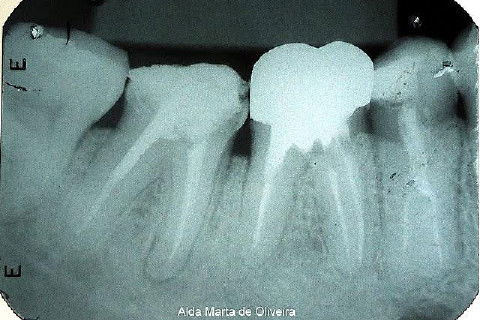

Paciente de 46 anos, encaminhado por uma colega para que eu instalasse um pino e fizesse um núcleo de preenchimento no dente 47.